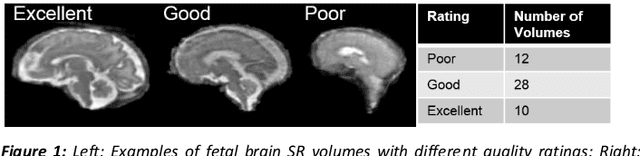

Abstract:Segmentation is a critical step in analyzing the developing human fetal brain. There have been vast improvements in automatic segmentation methods in the past several years, and the Fetal Brain Tissue Annotation (FeTA) Challenge 2021 helped to establish an excellent standard of fetal brain segmentation. However, FeTA 2021 was a single center study, and the generalizability of algorithms across different imaging centers remains unsolved, limiting real-world clinical applicability. The multi-center FeTA Challenge 2022 focuses on advancing the generalizability of fetal brain segmentation algorithms for magnetic resonance imaging (MRI). In FeTA 2022, the training dataset contained images and corresponding manually annotated multi-class labels from two imaging centers, and the testing data contained images from these two imaging centers as well as two additional unseen centers. The data from different centers varied in many aspects, including scanners used, imaging parameters, and fetal brain super-resolution algorithms applied. 16 teams participated in the challenge, and 17 algorithms were evaluated. Here, a detailed overview and analysis of the challenge results are provided, focusing on the generalizability of the submissions. Both in- and out of domain, the white matter and ventricles were segmented with the highest accuracy, while the most challenging structure remains the cerebral cortex due to anatomical complexity. The FeTA Challenge 2022 was able to successfully evaluate and advance generalizability of multi-class fetal brain tissue segmentation algorithms for MRI and it continues to benchmark new algorithms. The resulting new methods contribute to improving the analysis of brain development in utero.